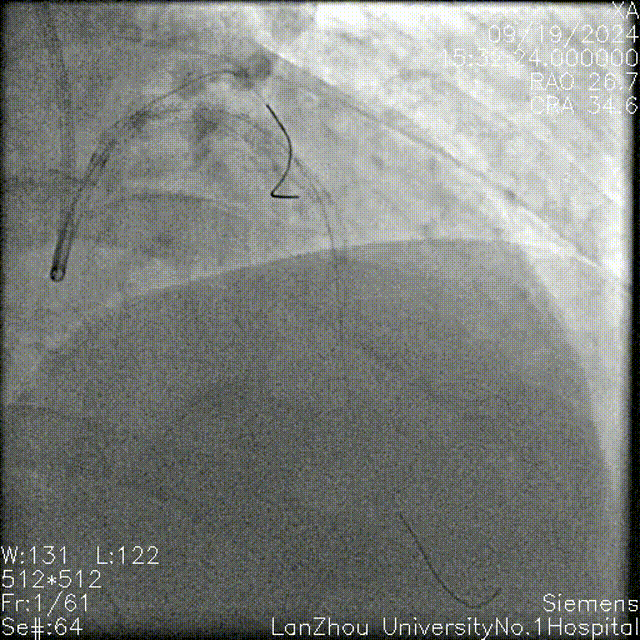

头位造影:

LM较短,末端可见重度狭窄,前降支近中段全程弥漫性狭窄伴钙化;

回旋支次全闭,可见钙化影。

右肩造影:

前降支近中段全程弥漫性狭窄伴环形钙化,最重处95%狭窄;

对角支开口狭窄不重,角度不大,可能不需要导丝保护。